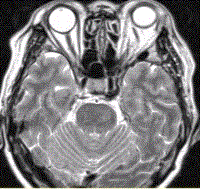

问题 女性,62岁。外伤后左侧突眼。MRI显示如下图。 关于该病,描述正确的是

选项 A.左侧眼上静脉增粗 B.左侧海绵窦增宽 C.左侧颈内动脉增粗 D.颈内动脉变细 E.左侧眼球突出 F.右侧颈内动脉增粗

答案 ABCE